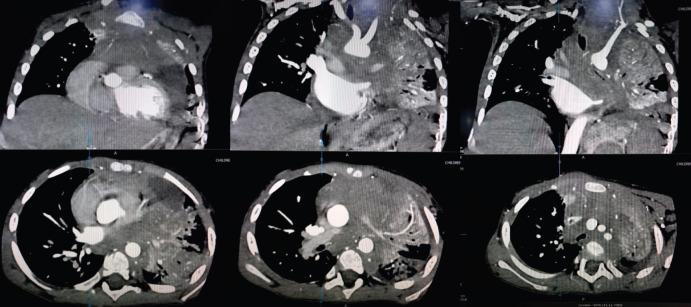

Superior mediastinal syndrome secondary to an anterior mediastinal mass can be seen in acute lymphoblastic leukaemia (ALL) of T-cell lineage. We report a 3-year-old child with B-cell ALL, who presented with the superior mediastinal syndrome. The CT scan chest showed a huge anterior mediastinal mass and the peripheral blood immunophenotyping showed B-cell ALL. High-risk remission induction chemotherapy was given and he achieved remission by the end of induction therapy, both in terms of medullary and extramedullary disease, and is on maintenance chemotherapy now. This is the first reported case of a paediatric B-cell ALL presenting with superior mediastinal syndrome secondary to an anterior mediastinal mass.

T细胞系急性淋巴细胞白血病(ALL)可出现继发于前纵隔肿块的上腔静脉综合征。我们报告1例3岁B细胞ALL患儿,该患儿表现为上腔静脉综合征。胸部CT扫描显示前纵隔巨大肿块,外周血免疫表型分析显示为B细胞ALL。给予高危缓解诱导化疗,诱导治疗结束时患儿达到缓解,髓内和髓外疾病均获缓解,目前正在进行维持化疗。这是首例报道的小儿B细胞ALL继发前纵隔肿块导致上腔静脉综合征的病例。